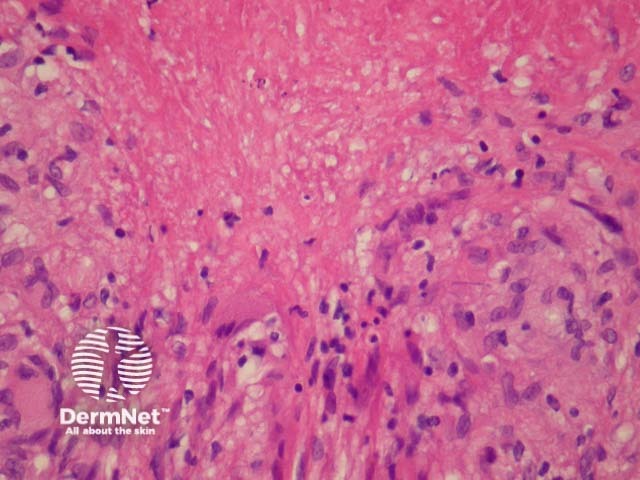

In LMDF, sections show round granulomas with central caseating necrosis. The granulomas may appear sarcoidal or tuberculoid. The granulomas typically arise adjacent to adnexal structures. A chronic infiltrate often accompanies the granulomas. See figures 1-4.

Figure 4